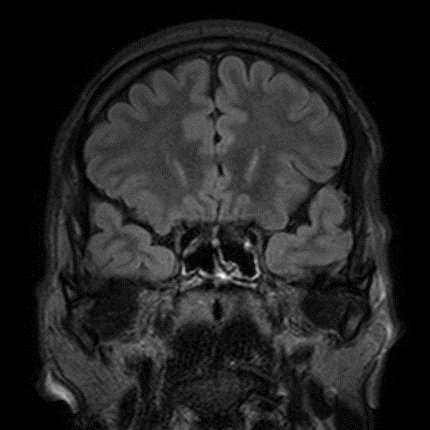

The Temporal Lobe Epilepsy (TLE) with hippocampal sclerosis affects other mesial temporal lobe structures, showing the change in signal intensity of white matter (WM) and gray matter (GM) in Magnetic Resonance Imaging (MRI) in patients with TLE.

Such abnormalities of signal intensity changes in the temporal lobes, or loss of marking between WM and GM are referred as blurring in literature.

This project will investigate the presence and location of the epileptogenic focus in temporal lobe by analyzing patterns of texture in magnetic resonance imaging (MRI) after segmentation using anisotropic diffusion filters anomalous and geodesic active contour.

Normal MRI at mesial temporal lobe

MRI containing blurring phenomena on right side as indicated by the yellow arrow